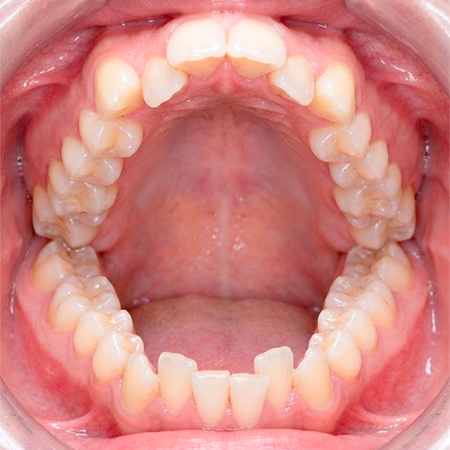

歯がガタガタしているところを放置した場合

歯が密集している真ん中は歯ブラシをあてるのは困難であり、フロスですらしっかりと充てるのは難しい場所になります。

こうした部位の虫歯の管理は患者さん自身の歯ブラシや歯科医院の定期管理ですら、難しいです。そのため、早期の治療、つまり矯正治療により管理しやすい状態にすることが大事です。